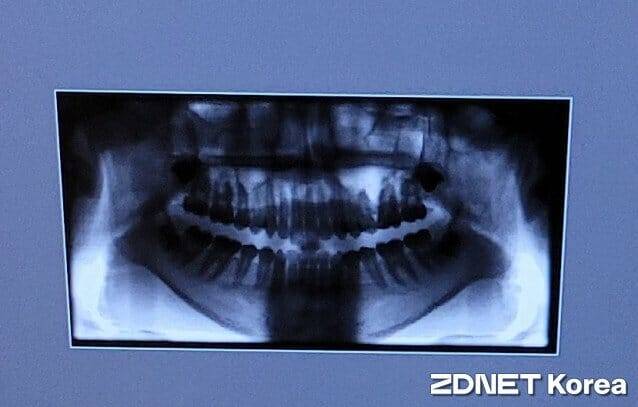

(지디넷코리아=조민규 기자)골다공증 치료제를 투여하는 환자의 경우 발치 후 턱뼈 괴사 위험이 높아지는 만큼 약물 중단을 고려해야 한다는 연구가 발표됐다.

분당서울대병원 내분비대사내과 공성혜 교수와 치과 이효정 교수팀이 골다공증 치료제의 투여 시점과 치아 발치 간의 간격이 길수록 약물 관련 턱뼈 괴사(MRONJ) 위험이 감소한다는 연구 결과를 발표했다.

하지만 골 흡수가 지나치게 억제되면 낡은 뼈가 잘 제거되지 않고 손상이 누적돼 턱뼈 괴사나 비전형 대퇴골 골절 등의 부작용이 발생할 수 있다. 특히 턱뼈는 일상 자극이 많은 부위로 골 흡수가 억제된 상태에서 발치‧임플란트 등 외과적 처치를 받으면 회복이 지연돼 괴사로 이어지기 쉽지만, 발치 전 비스포스포네이트 중단 시점에 대한 근거가 부족해 명확한 임상 지침이 마련되지 못한 상태였다.